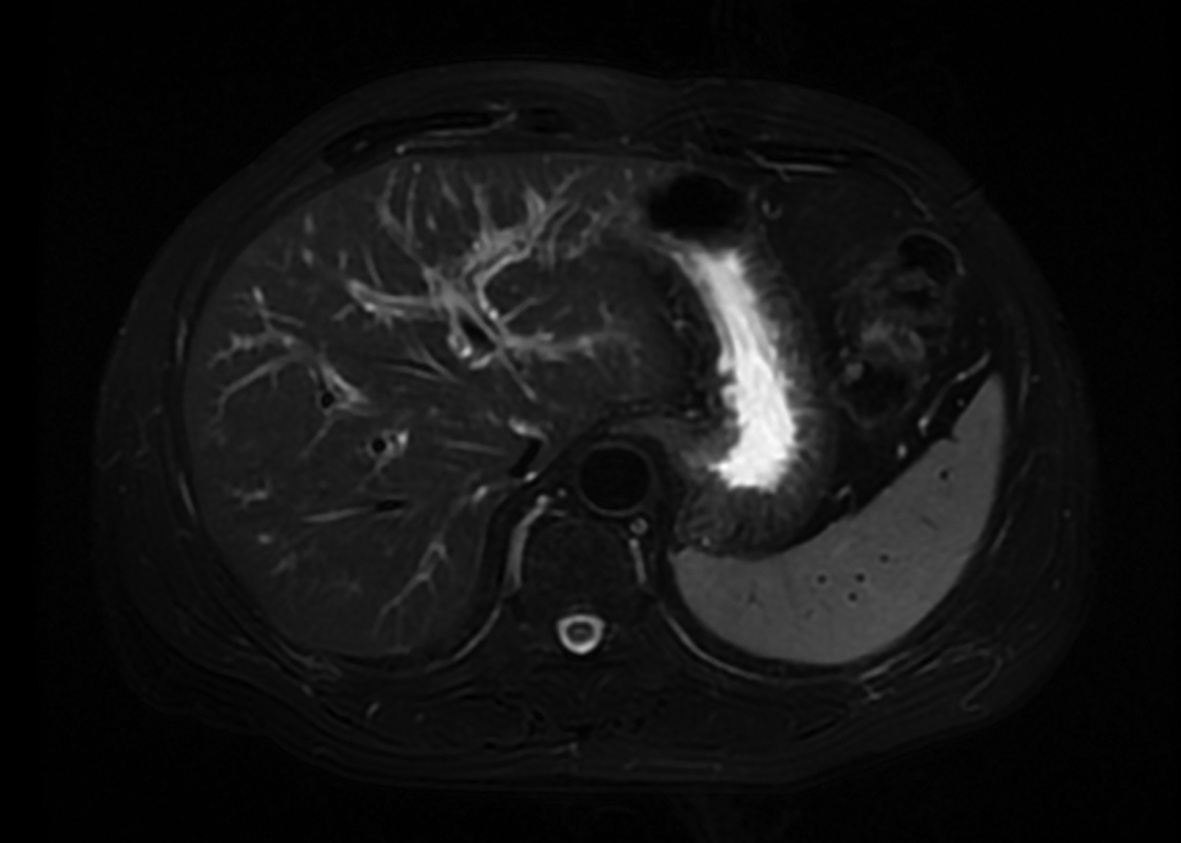

Local embolization combined with targeted comprehensive immunotherapy in treatment of sarcomatoid hepatocellular carcinoma: A case report

Jin LEI, Linzhi ZHANG, Yinying LU, Bowen CHEN, Shi ZUO

2022, 38(4): 880-882. DOI: 10.3969/j.issn.1001-5256.2022.04.026

Abstract(1335) HTML (456) PDF (3487KB)(84)

Abstract: